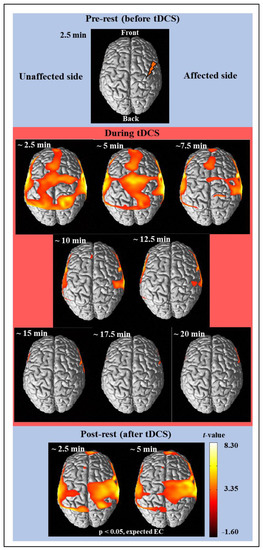

3.1. Activation Analysis Results Using NIRS-SPM